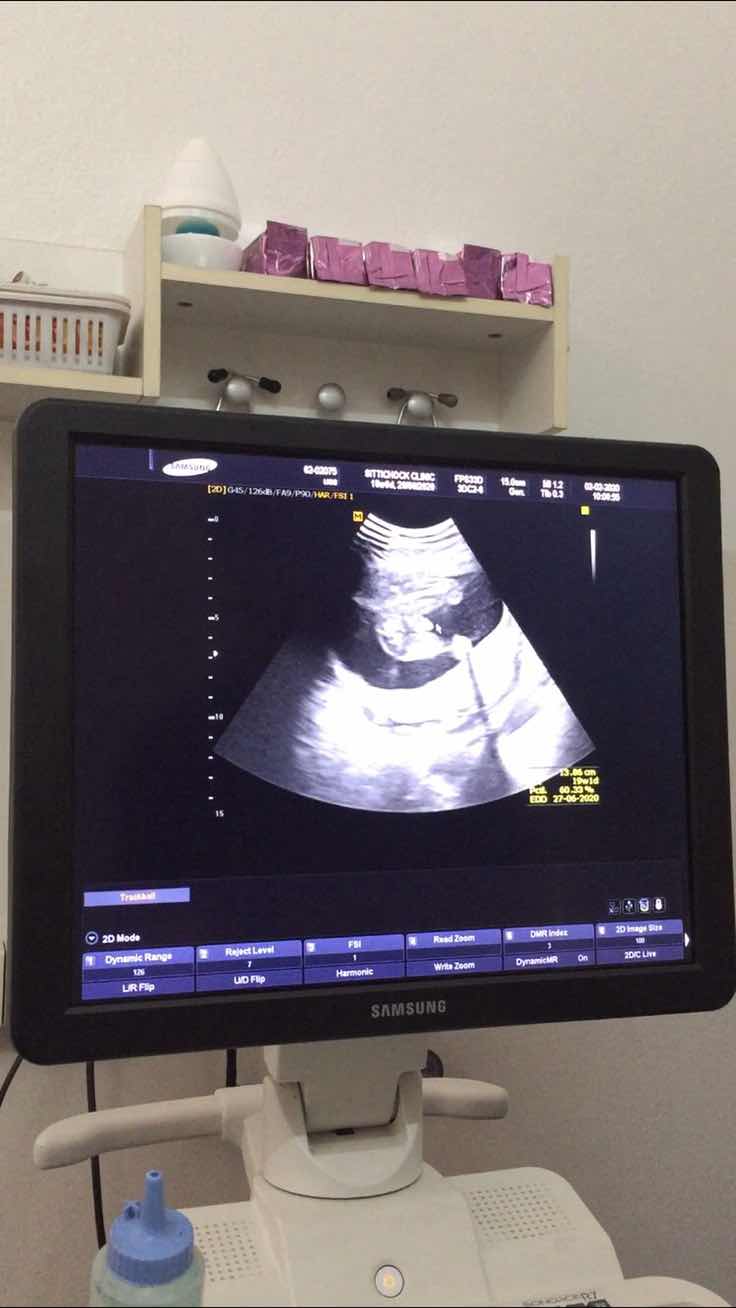

ผู้ชายค่ะ 31+5 วีค

ของบ้านนี้จ้า

หมอบอก ผช. ค่ะ